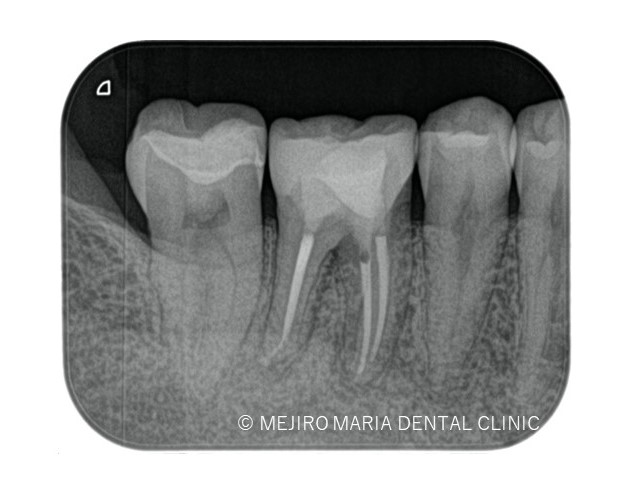

根管治療終了後1ヶ月後に経過観察を行い、術前に確認されていた限局的な歯周ポケットは正常範囲の値まで回復したのを確認したため、最終補綴を行った。

3ヶ月後のレントゲン撮影にて根尖病変の縮小、ならび違和感の消失を確認。今後最低2年間の経過観察(1年に1回)を行い、根尖周囲組織の治癒を確認していく。